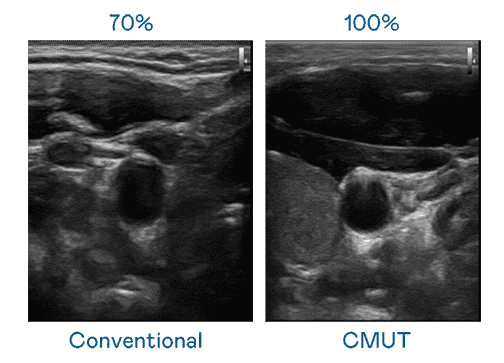

CMUT 技术是一种用电容式微机电元件来产生超音波讯号的技术。。。与传统 PZT 压电式技术相比,,,CMUT 频宽增加 30%,,,更宽频的超音波讯号让影像解析度大幅提升,,,是实现高影像品质医疗超音波扫描、、促进精准医疗发展的关键技术。。。。

大频宽带来超清晰影像

超音波影像的解析度高低,,首先取决于探头能发出的讯号频宽。。万利 CMUT 可提供高清晰的超音波讯号,,,,提供高频宽、、、高灵敏度、、、、影像纹理细节更高的超音波影像,,协助医护人员缩短影像判读时间及利用精准的医疗影像进行诊断。。